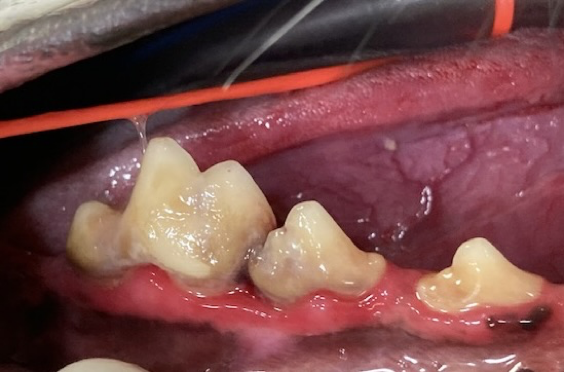

By three years old most dogs and cats have evidence of periodontal disease, an infection caused by bacteria in the tissues surrounding and supporting the teeth. The most prevalent sign of PD is bad breath.

Periodontal disease is a painful infection that, if left untreated, will progress to bone loss, mobile teeth, and eventually tooth loss. PD can lead to larger, more severe issues, such as jaw fracture due to bone loss and bone infection.

Periodontal disease is not always apparent during an initial consultation because it mainly occurs under the gum line. A complete exam is conducted under general anesthesia to evaluate each tooth for periodontal disease and the tissues that surround it.

Generally, this is determined by probing, charting, and radiographs. Without these diagnosis tools, these painful problems will remain undetected.